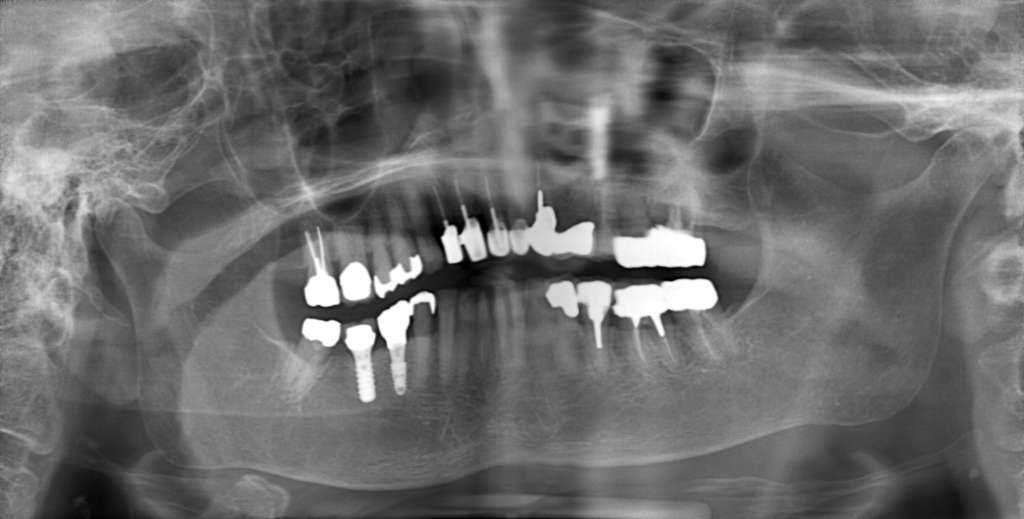

Y様インプラント実例 #44

左の上下の奥歯をインプラントで治療しています。

左下の奥歯は歯を抜くのと同時にインプラントの埋め込みを行っています。

被せものは上下、セラミックスで作っています。

治療前

治療後